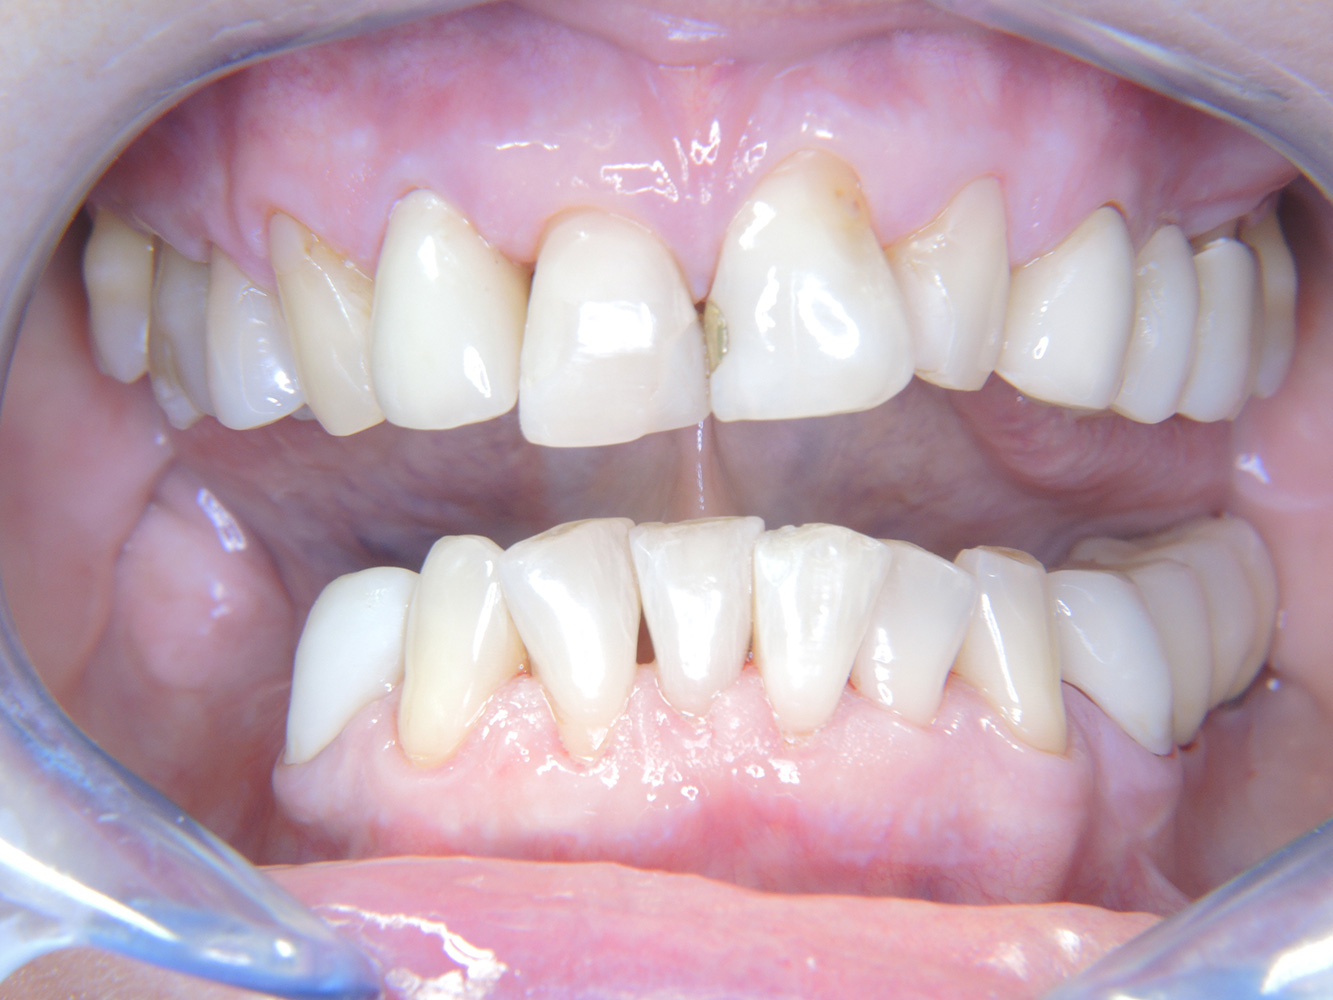

Nonostante le condizioni stabili, anche per questa paziente non si può rinunciare a un colloquio motivazionale/istruttivo. In particolare, bisogna insegnare alla paziente come prendersi cura correttamente del proprio impianto. Nella sua situazione, infatti, una buona igiene domestica può

influire molto sulla stabilità a lungo termine della sua salute orale e dell'impianto.

Per quanto riguarda gli strumenti, per gli impianti servono procedure specifiche. Al fine di preservare la superficie dell'impianto e al tempo stesso pulirlo in maniera efficace, è fondamentale scegliere le polveri e gli strumenti giusti come l'impiego mirato di air-polisher con speciali punte Paro. La scelta della polvere più adatta viene fatta tenendo in considerazione esigenze e rischi. Ad esempio, oltre al giusto grado di abrasività, si possono valutare anche aspetti legati all'alimentazione (tra cui alimenti privi di zucchero, a basso contenuto di sale).